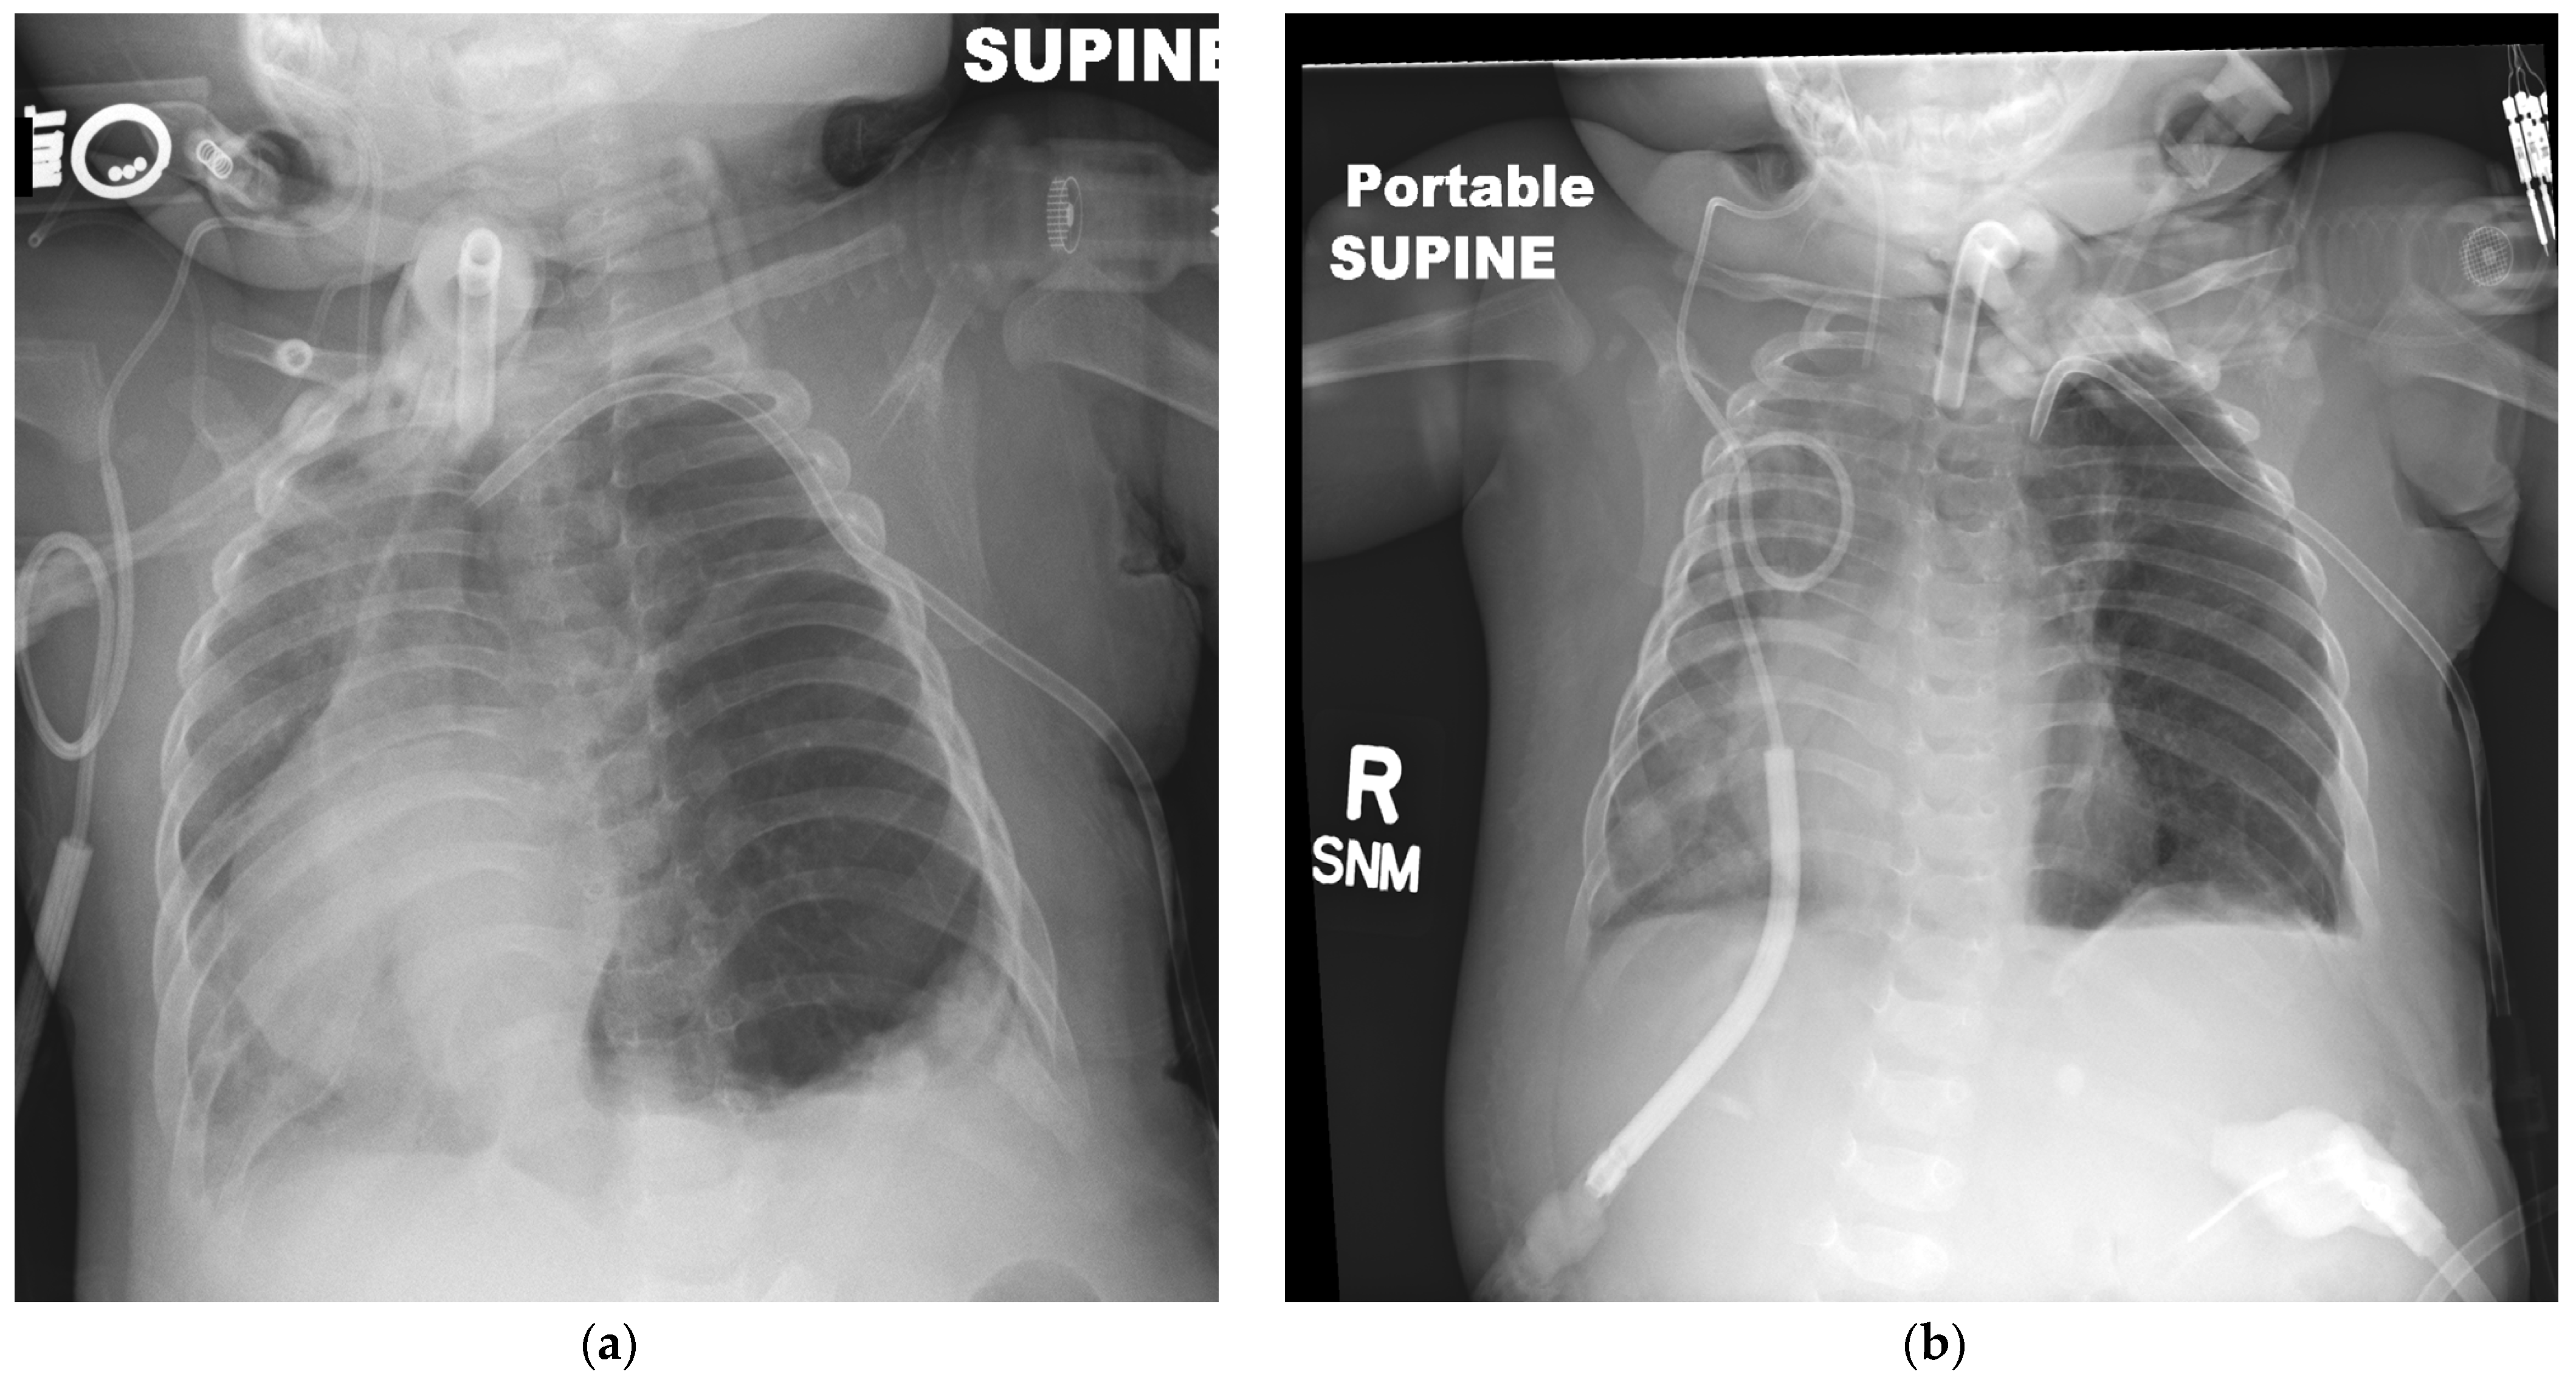

2. Case Presentation